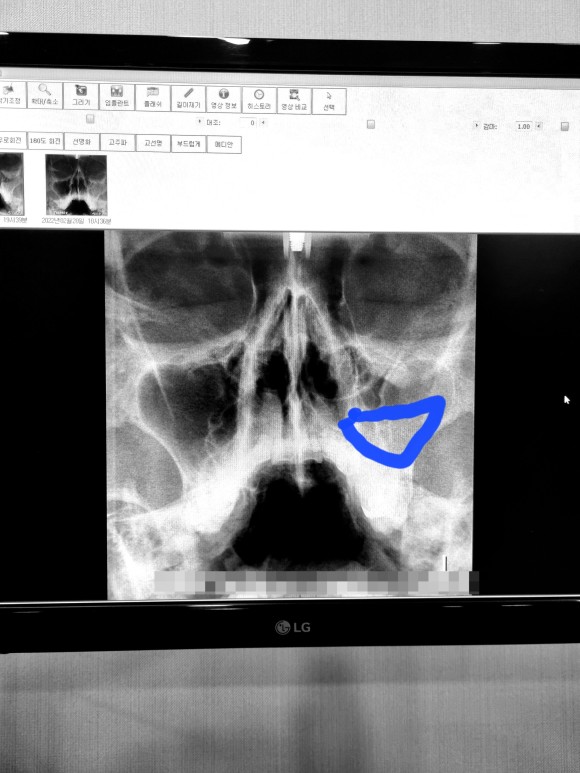

부비강염

잘 구별하기는 힘들겠지만 오른쪽을 보시면

절반이나 염증이 없어진 것을 확인할 수 있다.

정말 다행이야